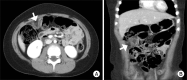

Epiploic appendagitis is an inflammation of the epiploic appendage in which the small sacs projecting from the serosal layer of the colon are positioned longitudinally from the caecum to the rectosigmoid area. Epiploic appendagitis is rare and self-limiting; however, it can cause sudden abdominal pain in children. Epiploic appendagitis does not typically accompany other gastrointestinal diseases. Here, we report on a healthy eight-year-old girl who presented with abdominal pain, fever, vomiting, and diarrhea. Based on these symptoms, she was diagnosed with acute gastroenteritis, but epiploic appendagitis in the ascending colon was revealed in contrast computed tomography (CT). The patient was treated successfully with conservative management. CT is beneficial in diagnosis and further assessment of epiploic appendagitis. Pediatricians need to be aware of this self-limiting disease and consider it as a possible alternate diagnosis in cases of acute abdominal pain.